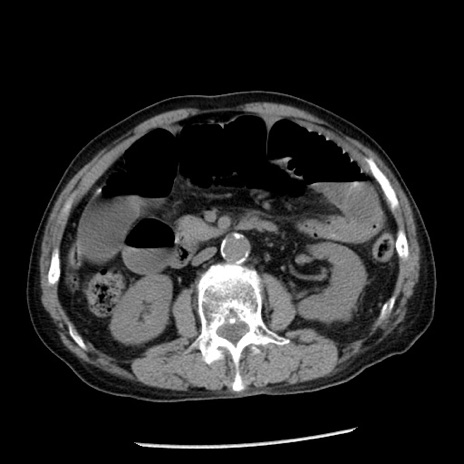

冠状断像

【症例】80歳代男性

【主訴】嘔吐

【現病歴】昨晩2回嘔吐あり、今朝になっても嘔吐あり。来院。

【既往歴】胃潰瘍

【身体所見】意識清明、BT 37.6℃、BP 166/95mmHg、HR 100bpm、SpO2 97%、腹部:平坦・軟、腸蠕動音聴取良好、圧痛なし。

【データ】WBC 21900、CRP 1.46